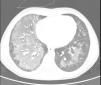

The high resolution chest CT scan (Fig. 1) showed central areas of confluent ground-glass hyperattenuation with superimposed interlobular septal thickening, resembling a “crazy-paving” pattern. Bronchoalveolar lavage showed large amounts of hemosiderin-laden macrophages and surgical lung biopsy presented intra-alveolar hemosiderophages (Pearl's Prussian Blue staining) with septal thickening and fibrosis at some lobules, without evidence of capillaritis. These findings confirmed the diagnosis of IPH. Evaluation for milk protein allergy and celiac disease (Lane–Hamilton syndrome) were performed, due to their frequent association with IPH.